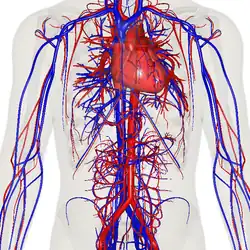

Кровеносная система человека. Красным обозначены артерии, синим — вены. Капиляры соединяют артерии с венами.

Циркулято́рная система, также система кровообращения и кровеносная система[1] — система органов, включающая сердце, кровеносные сосуды и кровь, которая циркулирует по всему телу человека или другого позвоночного[2][3]. Включает в себя сердечно-сосудистую систему (также кардио-васкулярная система от греческого kardia — сердце, и латинского vascula — сосуды), которая состоит из сердца и кровеносных сосудов. Кровеносная система состоит из большого и малого круга кровообращения[4].

Сеть кровеносных сосудов составляют магистральные сосуды сердца, включающие крупные артерии и вены, другие артерии и артериолы, а также капилляры, впадающие в венулы (мелкие вены), и другие вены. Кровеносная система у позвоночных замкнута, это значит, что кровь никогда не покидает сеть кровеносных сосудов. Некоторые беспозвоночные, такие как членистоногие, имеют открытую систему кровообращения. У диплобластов, таких как губки и гребневики, кровеносная система отсутствует.